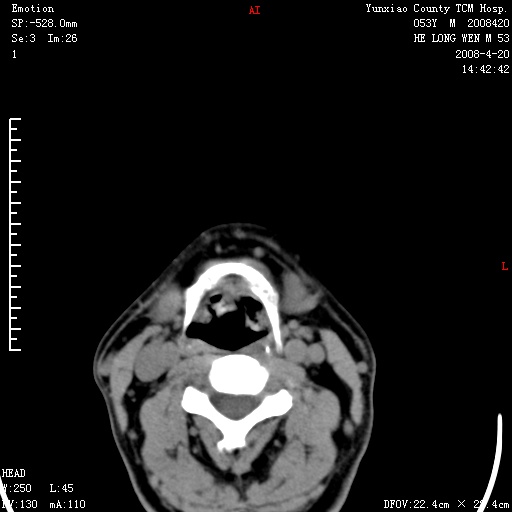

双侧扁桃体肿大:考虑化脓性扁桃体炎。

双侧扁桃体肿大 ,考虑扁桃体炎。

双侧扁桃体肿大,建议结合临床!

双侧扁桃体肿大 ,考虑扁桃体炎

应该有症状,体检此部位不是常规体检项目,支持双侧扁桃体肿大 ,考虑扁桃体炎,但还是强化一下吧。

双侧扁桃体肿大,考虑扁桃体炎,应做一下增强

显示部分为舌扁桃体,腭扁桃体未见显示。会厌显示欠规则,建议喉镜。